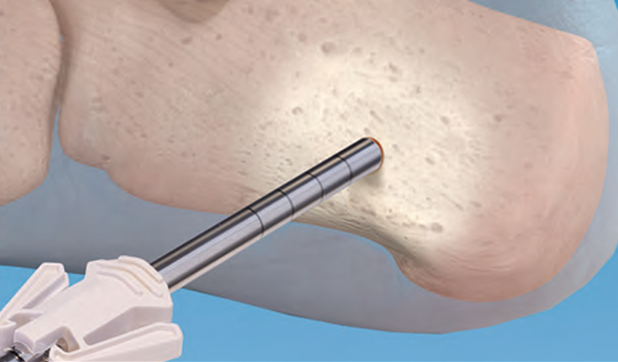

Unleash Your Precision

A cordless small bone power system designed with comfort in mind. High-performance Lithium-ion technology provides the power you need, while convenient one-step sterilization adds operational value.